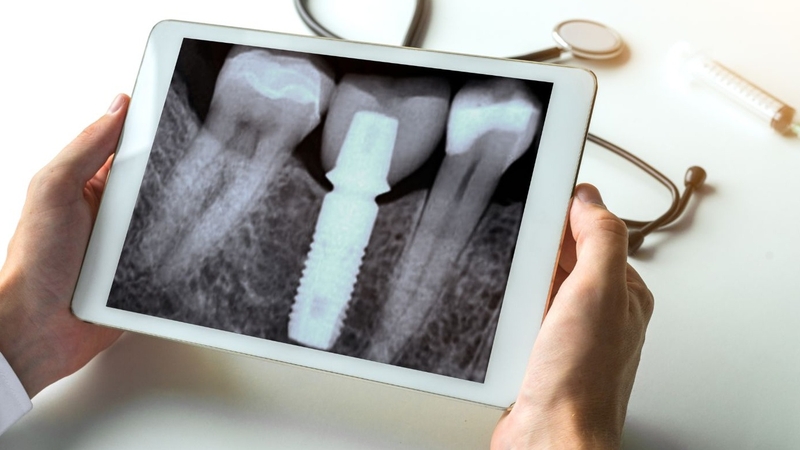

Chụp X quang răng cận chóp còn được gọi là chụp phim sau huyệt ổ răng được chỉ định trong thăm khám răng hàm mặt. Kỹ thuật này giúp bác sĩ quan sát rõ nét và chi tiết về hình thái, cấu trúc một răng và các cấu trúc lân cận.

X quang răng cận chóp hay X quang sau huyệt ổ răng thường được chỉ định khi bệnh nhân thăm khám răng lần đầu. Hình ảnh thu được từ chụp X quang sau huyệt ổ răng sẽ cho bác sĩ biết một cách rõ ràng, chi tiết về cấu trúc, hình thái, hướng mọc của răng. Hình chụp X quang cũng phản ánh các tổn thương lân cận quanh răng như ống dây thần kinh, mạch máu, lợi (nếu có).

Kết quả chụp X quang sẽ giúp bác sĩ đưa ra chẩn đoán ban đầu và xác định phương pháp điều trị cho vấn đề về răng một cách phù hợp. Dù là một kỹ thuật chụp X quang răng đã ra đời từ rất lâu đời với giá thành rẻ hơn nhưng hiệu quả không kém gì các kỹ thuật chụp hiện đại.